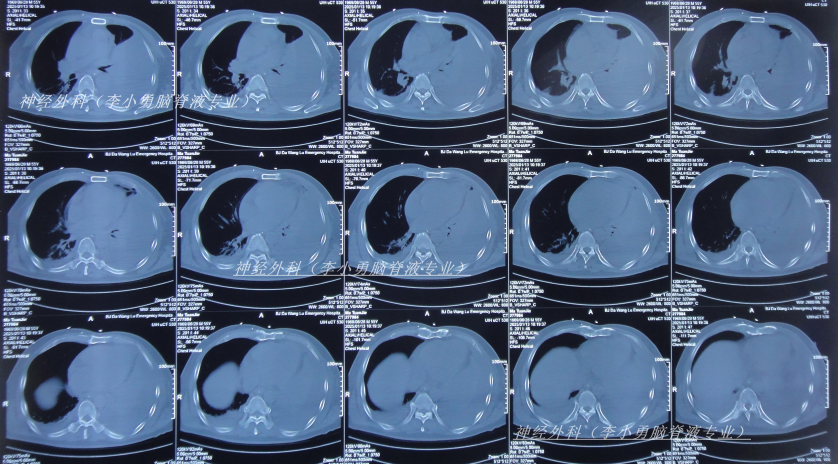

入院当天查头颅CT示颅脑术后改变,脑室扩张,双侧额部硬膜下积液(图-12);胸部CT示两肺炎性病变,心包积液,双侧胸腔积液(图-13)。

图-12:2025年2月4日头颅CT

图-13:2025年2月4日胸部CT